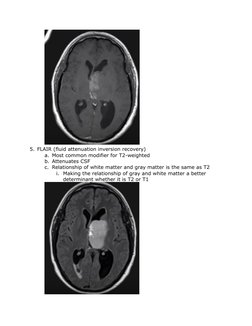

5. FLAIR (fluid attenuation inversion recovery)

a. Most common modifier for T2-weighted

b. Attenuates CSF

c. Relationship of white matter and gray matter is the same as T2

i. Making the relationship of gray and white matter a better

determinant whether it is T2 or T1